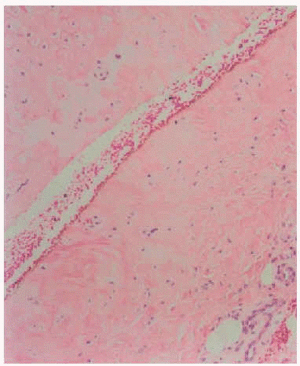

Se realizó inicialmente una punción-aspiración con aguja fina (PAAF), obteniéndose líquido amarillento sin contenido epitelial. De la biopsia de ambas lesiones se obtuvo idéntico resultado: edema pericondral con mínimo infiltrado perivascular linfocitario y una cavidad intracartilaginosa sin revestimiento epitelial.

Fig. 2.--Histología correspondiente a la figura 1, que encuentra una seudocavidad intracartilaginosa.